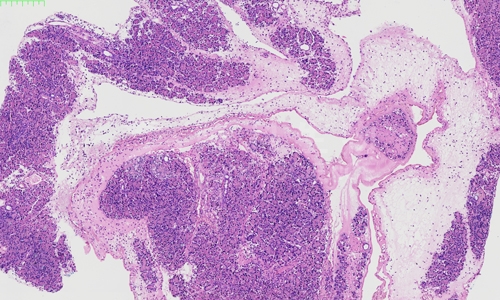

在病理学领域,HE染色(Hematoxylin and Eosin Staining)作为一种经典的染色方法,被广泛应用于组织样本的观察和分析。HE染色不仅为病